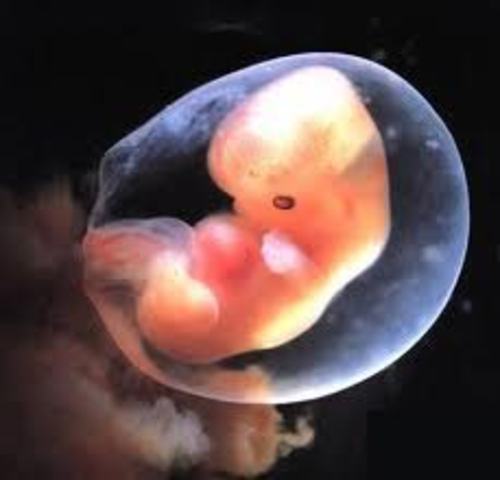

• Week 7

Week 7

The heart is now in service! The embryo has developed its placenta and amniotic sac. The placenta is burrowing into the uterine wall to access oxygen and nutrients from the mother’s bloodstream.